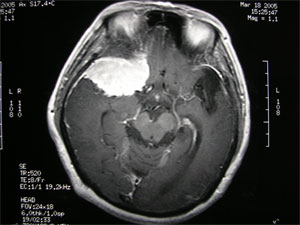

5.CT和MRI掃描 可確定腫瘤的部位和大小,絕大多數可作出定性診斷。CT掃描示邊界清晰的均勻高密度影,增強後顯著。少數呈混合密度或低密度改變。MRI見腫瘤多數呈等信號,增強後明顯強化。

2.MRI掃描 MRI對診斷本病是有意義的MRI可以顯示腫瘤與蝶骨翼和眼眶的關係骨質破壞情況等。尤其是對內側型的蝶骨嵴腦膜瘤MRI還可以提供腫瘤與頸內動脈的關係有時腫瘤將頸內動脈包裹在內或腫瘤附著在海綿竇上這些情況對手術切除腫瘤均有重要的參考價值增強後的MRI圖像更清晰。